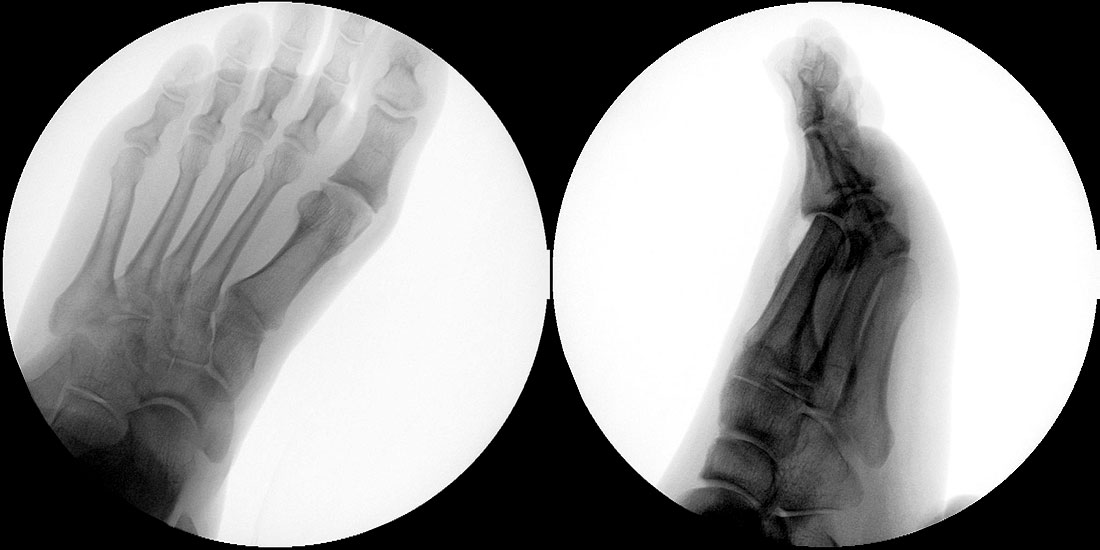

Klinisch zeigt sich stadienabhängig eine schmerzhafte Bewegungseinschränkung mit zunehmender Steifigkeit des Großzehengrundgelenkes. Vor allem die Einschränkung der Dorsalextension wird von den Patienten oft als unangenehm empfunden. Initial besteht eine bindegewebige Alteration im Gelenk, im weiteren Stadium treten Knorpeldegeneration und Begleitsynovialitis mit der Ausbildung von osteophytären Randanbauten auf. Klinische treten diese meist durch eine schmerzhafte dorsale Knochenkante in Erscheinung (Abbildung 1).

Im späten Stadium imponiert eine Gelenkblockierung durch freie Gelenkkörper. Während in den Anfangsstadien vor allem die dorsalen Anteile des Gelenks betroffen sind, betreffen die Veränderungen in den Fortgeschrittenen Stadien die gesamte Zirkumferenz einschließlich des Sesambeingleitlagers. Im Endstadium kommt es zu einer weitgehenden Ankylosierung des 1. Metatarsophalangealgelenks.

Die Cheilektomie ist indiziert vor allem im Stadium II der Erkrankung, in welchem die degenerativen Veränderungen vor allem auf die dorsalen Gelenkanteile konzentriert sind und sich in der plantaren Gelenkhälfte noch ein ausreichender Knorpelbelag findet 48. Der Eingriff umfasst die Synovektomie, die Entfernung von freien Gelenkkörpern und die Abtragung von dorsalen, lateralen und medialen Osteophyten am Metatarsale I Kopf und an der Grundgliedbasis. Zusätzlich kann eine offene Arthrolyse des Sesambeingleitlagers durchgeführt werden. Ziel ist eine Schmerzreduktion durch Abtragung der Ostepohyten mit Verbesserung der Beweglichkeit des 1. Metatarsophalangealgelenkes. Dieses Operationsverfahren kann auch im Stadium III der Erkrankung durchgeführt werden, allerdings ist dann häufiger mit Restbeschwerden und einer signifikant verlängerten Rehabilitationszeit zu rechnen 9.

• Röntgenaufnahme des Fußes in drei Ebenen unter Belastung